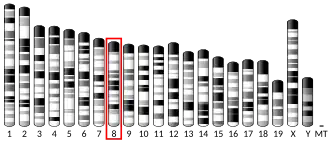

The norepinephrine transporter gene, SLC6A2 is located on human chromosome 16 locus 16q12.2. This gene is encoded by 14 exons.[7] Based on the nucleotide and amino acid sequence, the NET transporter consists of 617 amino acids with 12 membrane-spanning domains. The structural organization of NET is highly homologous to other members of a sodium/chloride-dependent family of neurotransmitter transporters, including dopamine, epinephrine, serotonin and GABA transporters.[7]